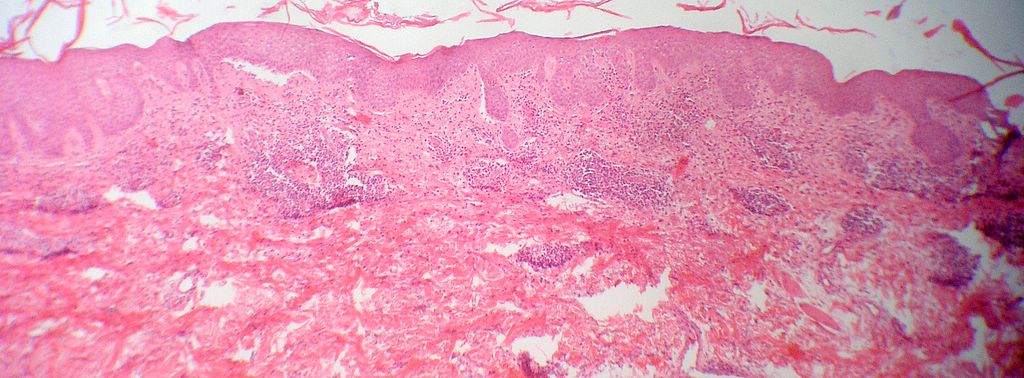

Biopsia (14066)que muestra los cambios que observas en las imágenes.

Descripción histológica

Diagnóstico